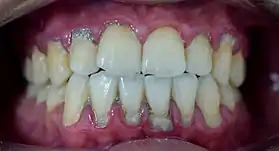

In dentistry, calculus or tartar is a form of hardened dental plaque. It is caused by precipitation of minerals from saliva and gingival crevicular fluid (GCF) in plaque on the teeth. This process of precipitation kills the bacterial cells within dental plaque, but the rough and hardened surface that is formed provides an ideal surface for further plaque formation. This leads to calculus buildup, which compromises the health of the gingiva (gums). Calculus can form both along the gumline, where it is referred to as supragingival ("above the gum"), and within the narrow sulcus that exists between the teeth and the gingiva, where it is referred to as subgingival ("below the gum").

Calculus formation is associated with a number of clinical manifestations, including bad breath, receding gums and chronically inflamed gingiva. Brushing and flossing can remove plaque from which calculus forms; however, once formed, calculus is too hard (firmly attached) to be removed with a toothbrush. Calculus buildup can be removed with ultrasonic tools or dental hand instruments (such as a periodontal scaler).

Plaque accumulation causes the gingiva to become irritated and inflamed, and this is referred to as gingivitis. When the gingiva become so irritated that there is a loss of the connective tissue fibers that attach the gums to the teeth and bone that surrounds the tooth, this is known as periodontitis. Dental plaque is not the sole cause of periodontitis; however it is many times referred to as a primary aetiology. Plaque that remains in the oral cavity long enough will eventually calcify and become calculus.[15] Calculus is detrimental to gingival health because it serves as a trap for increased plaque formation and retention; thus, calculus, along with other factors that cause a localized build-up of plaque, is referred to as a secondary aetiology of periodontitis.